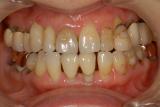

審美歯科治療 | ||

| 見た目の美しさだけにとらわれてはいけません。機能性を十分に満たした美しさが本当の審美歯科です。またそれが永続性のあるものでなければ意味がありません。歯グキの色素を除去し綺麗なピンク色にし、下の前歯を漂白し(両方とも殆ど痛みはありません)上の前歯にセラミック冠を被せました。 |

【治療前】 |

【治療後】 |